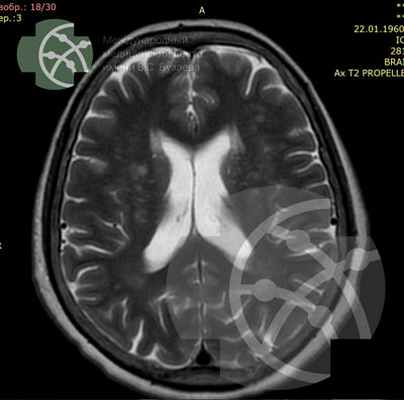

Добрый день! На протяжение последнего года периодически мучила головная боль. Сделала МРТ головного мозга, в заключение указали:

МР - картина мелкой кисты эпифиза

МР- картина дополнительного образования правой височной мыщцы, susp. с высокобелковым (серозно-гнойным) содержимым (с учетом сигнальных характеристик).

Подскажите пожалуйста, что делать и к какому специалисту нужно обратиться. Спасибо!